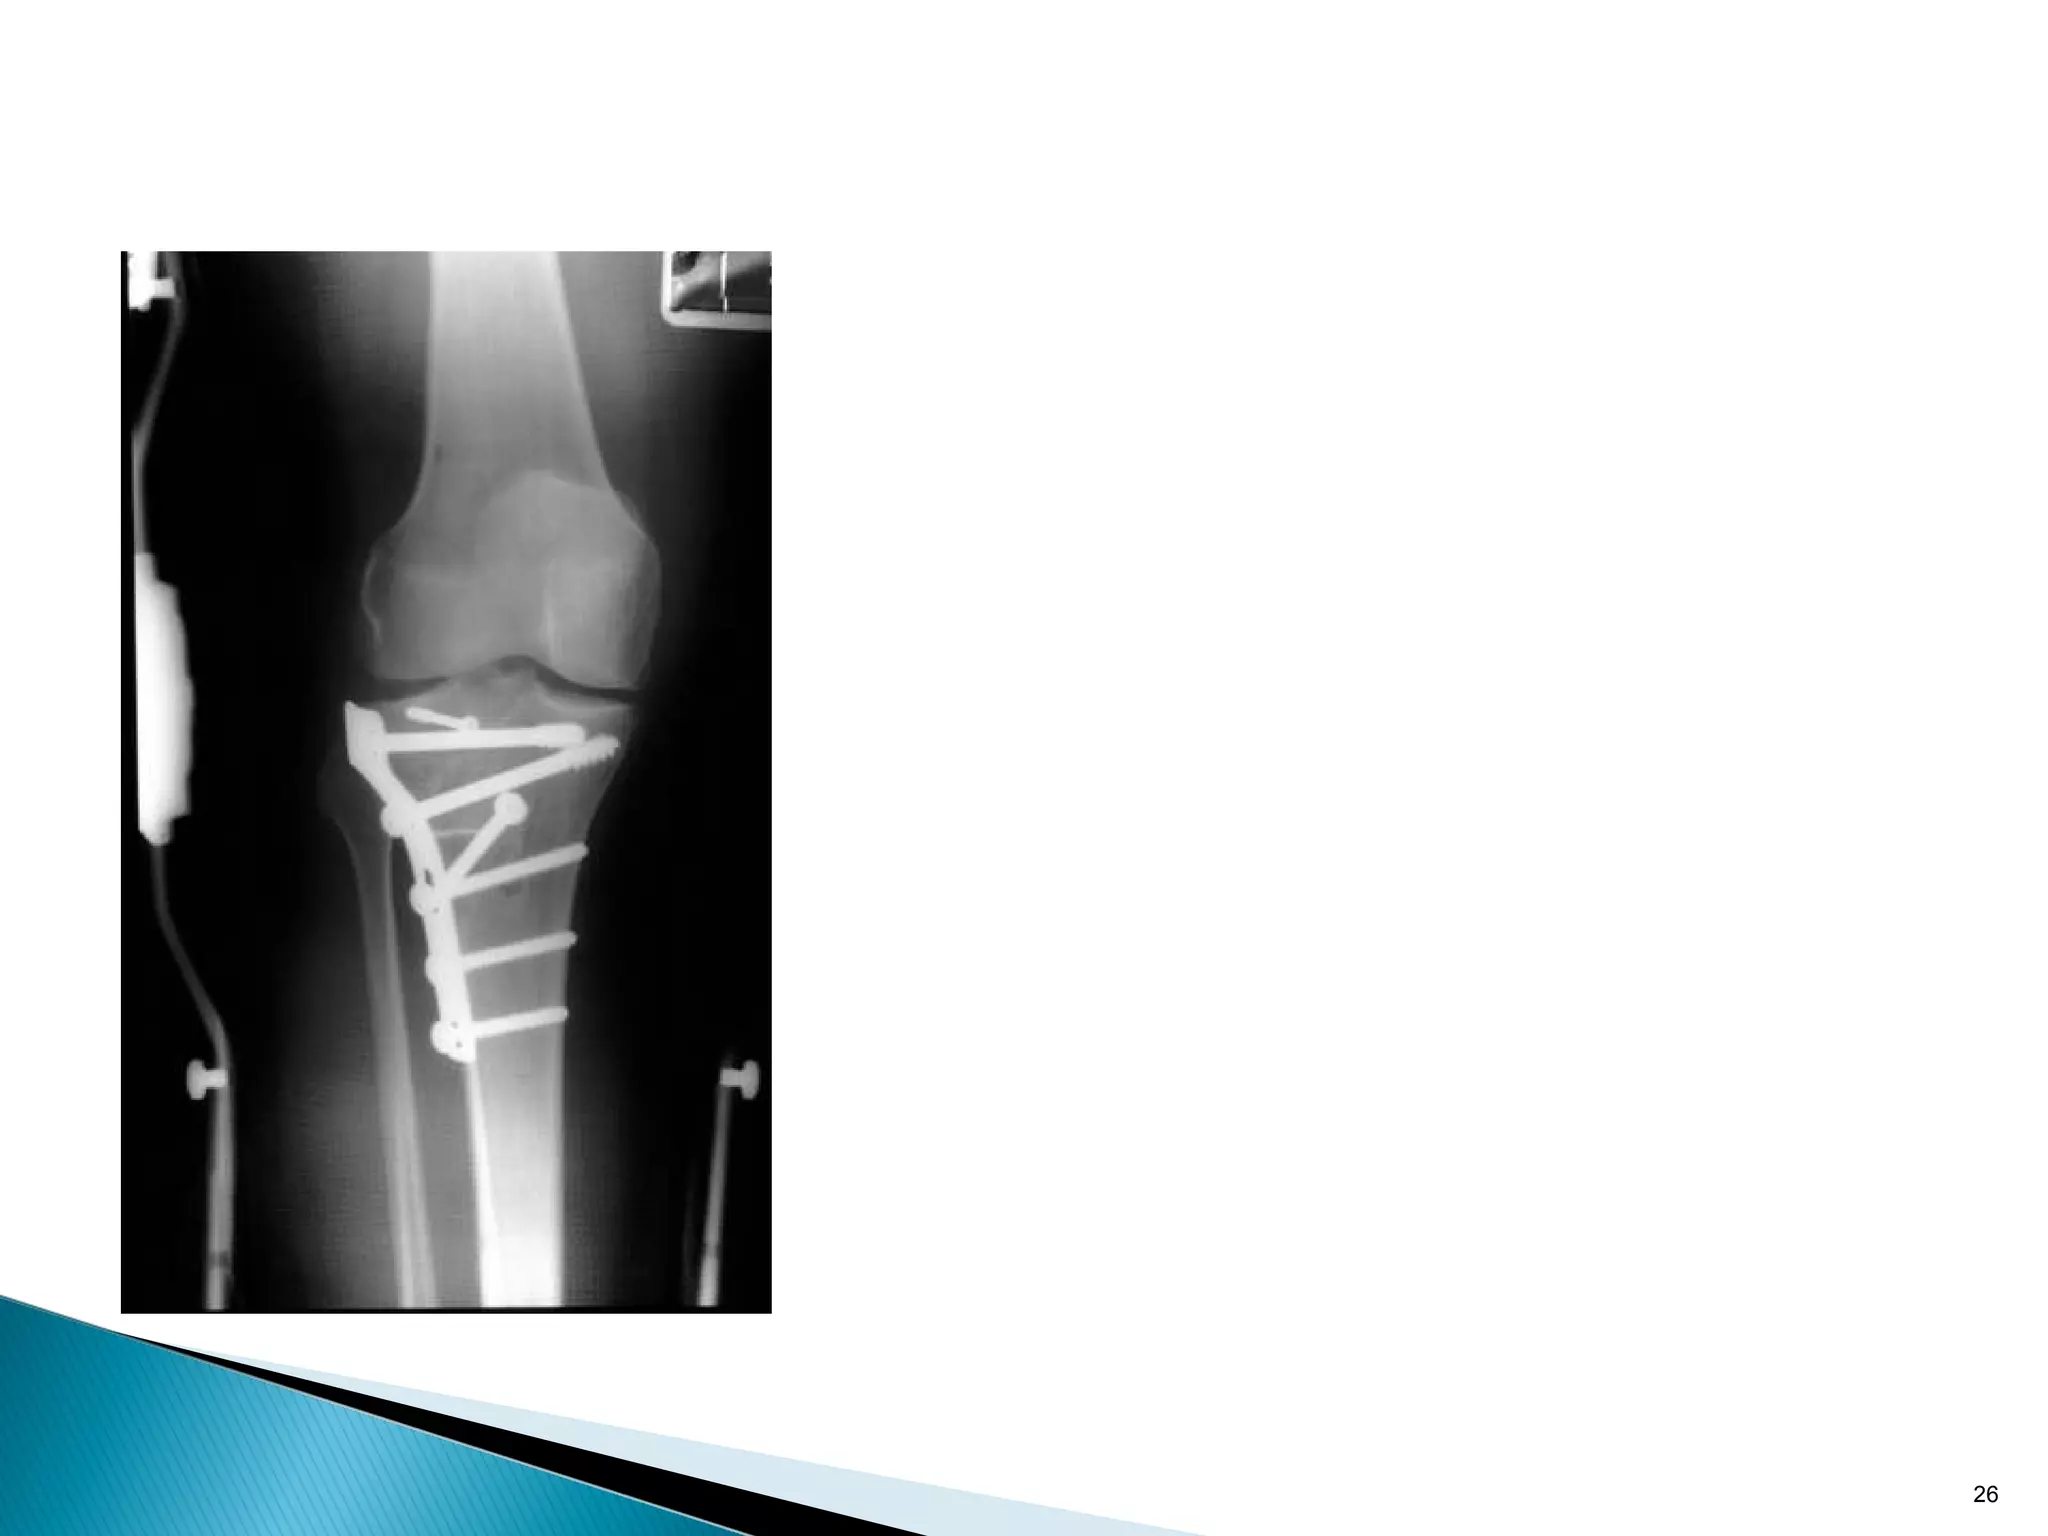

•Resist axial load by applying force at 90 degree to the axis of

potential deformity

•Metaphyseal tibial plateau split fractures

24

•Resist axial loadby applying force at 90 degree to the axis of potential deformity •Metaphyseal tibial plateau split fractures 24